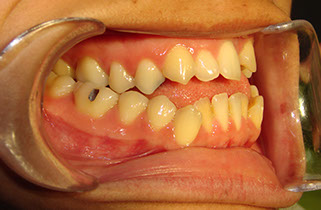

c.- Clase III, Al contrario que la anterior tenemos que los dientes inferiores están por delante  de los de arriba en este caso el problema esquelético es muy deformante facialmente, recibiendo el nombre técnico de progenie.